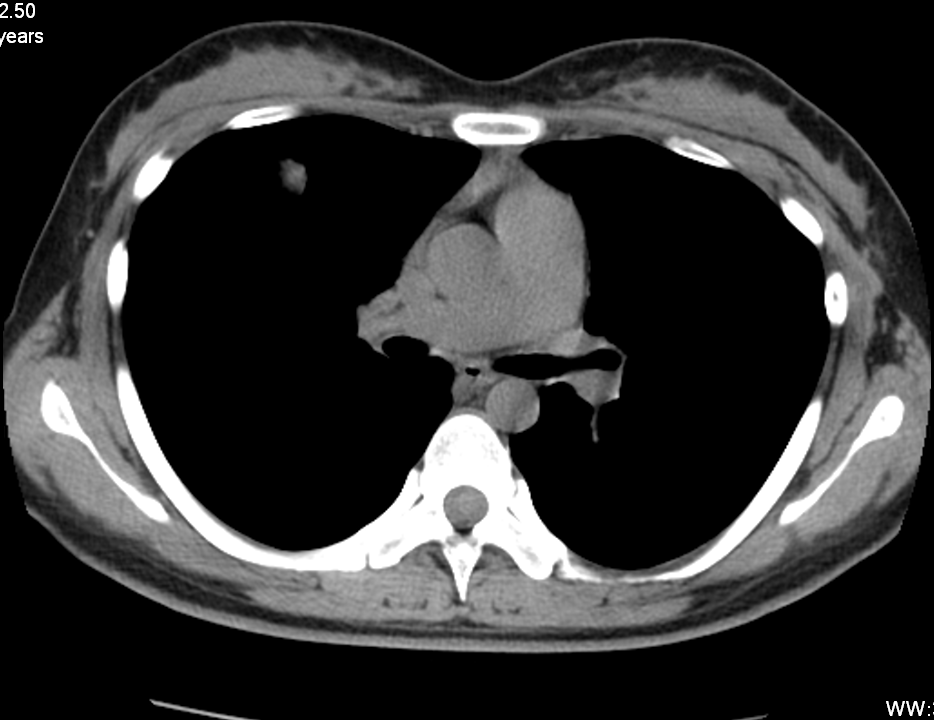

患者:女,25,询问病史体检前一周发热一天用抗炎药后体征恢复正常。曾接触患甲流患者。体检发现右肺结节影,嘱其抗炎治疗两周后复查,复查后示病灶明显缩小,考虑球形肺炎

1月6号胸片显示右肺结节

1月14日CT显示右肺中叶外侧段可见结节灶,毛刺,有索条河胸膜相连

3月7号抗病毒治疗后复查病灶明显吸收

1 肿瘤?

2结核?

3炎症?